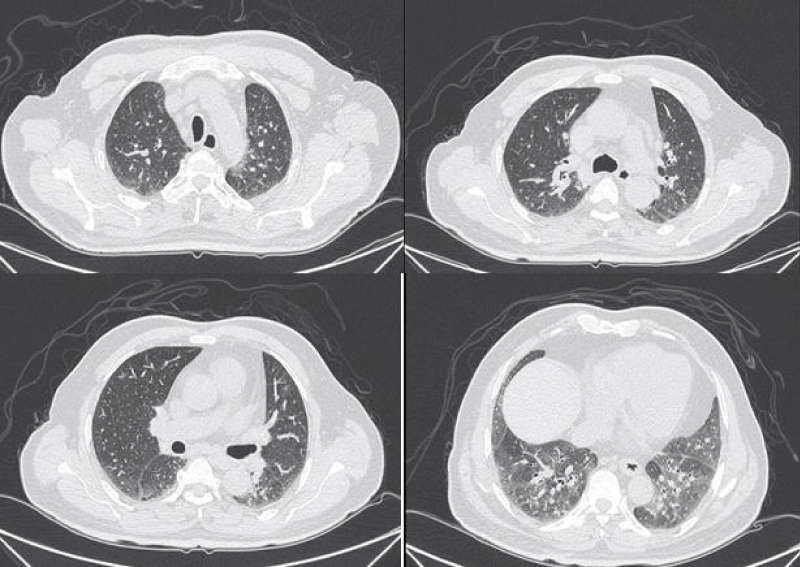

HRCT images

The most common presentation on HRCT were ground-glass opacities, showed 79.3% (92 patients). Secondly, 74.1% patients showed interlobular septal thickening, followed by reticular opacities(58.6%), intralobular interstitial thickening(45.7%), mediastinal lymph node enlargement(36.2%), nodules(30.2%), honeycomb cysts (29.3%), traction bronchiectasis(21.6%), stripes(17.2%), pleural thickening(14.7%), pleural effusion(10.3%), dilation of the esophagus(6.9%), emphysema(6.9%), bullae(5.2%), consolidation(5.2%), subpleural line(0.9%) (Figures 1-9).

Figure 1: Ground-glass opacities.

Figure 2: Interlobular septal thickening.

Figure 3: Intralobular septal thickening.

Figure 4: Reticular opacities.

Figure 7: Different levels HRCT images from a 65 year-old male considered as NSIP pattern.

Figure 8: Different levels HRCT images from a 54 year-old male considered as UIP pattern.

Figure 9: Different levels HRCT images from a 52 year-old male considered as LIP pattern.

HRCT represents a reliable, noninvasive and repeatable tool for detecting and monitoring ILD in patients with SSc. The main HRCT findings in SSc-ILD are signs of GGO, interlobular septal thickening, intralobular septal thickening, reticular opacities; honeycombing, traction bronchiectasis and nodules can also be observed.

GGO as the most common presentation on HRCT, were hazy increased attenuation of lung, presented nodular, piece-like round or irregular shape on HRCT, with preservation of bronchial and vascular margins, mainly distributed in the lung periphery or diffusely distributed symmetrical, always suggested the early-stage or active-stage [6,7].

Cells aggregating in the interlobular septa and intralobular septa with tissue fibrosing, it leaded to irregular thread-like opacities on HRCT, which interleave with each other to forming reticular opacities, distributing in base of the lung mainly [6].

Inflammatory cell infiltration in lung tissue, lymphedema and fibrous tissue hyperplasia pulled bronchus and bronchioles resulting in irregular bronchiectasis. Traction bronchiectasis were showed thickening of the wall, expansion the lumen as dual track or irregular bag-like changes [6].

Honeycomb cysts/honeycombing referred to multi-layered cystic airspaces of typically consistent diameter (3–10 mm, but occasionally larger) with thick, well-defined walls without normal lung architecture. These lesions were irreversible and mainly distributed in the base of both lungs and under the pleura, suggesting end-stage lesions [7].